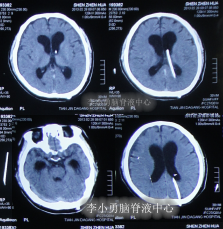

患者于2011年6月20日,因意外车祸致全身多器官损伤昏迷,当天住入天津著名的三甲脑科医院,检查明确颅脑外伤、肺挫伤、骨盆骨折(片子丢失),头部MRI和CT提示颅骨骨折,脑干弥漫性轴索损伤,颅内有出血,水肿(图-1、图-2)。

图-2:2011年6月20日头部CT

图-3:2011年6月20日头部CT